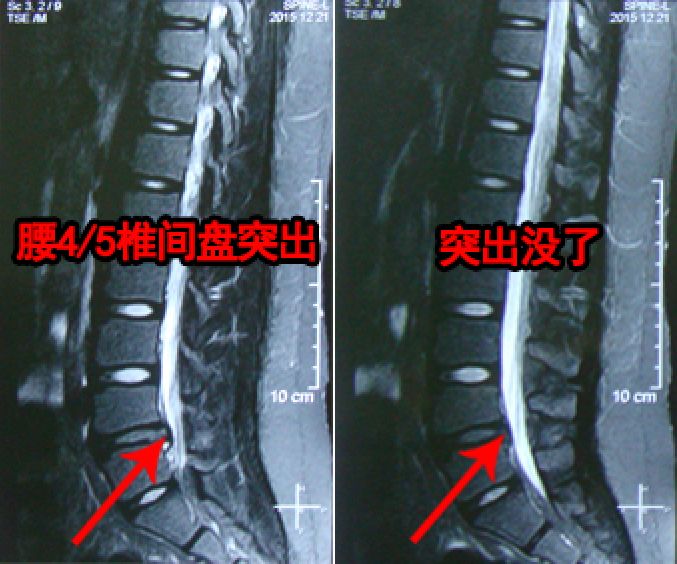

被诊断为轻度腰突

腰椎完全康复了